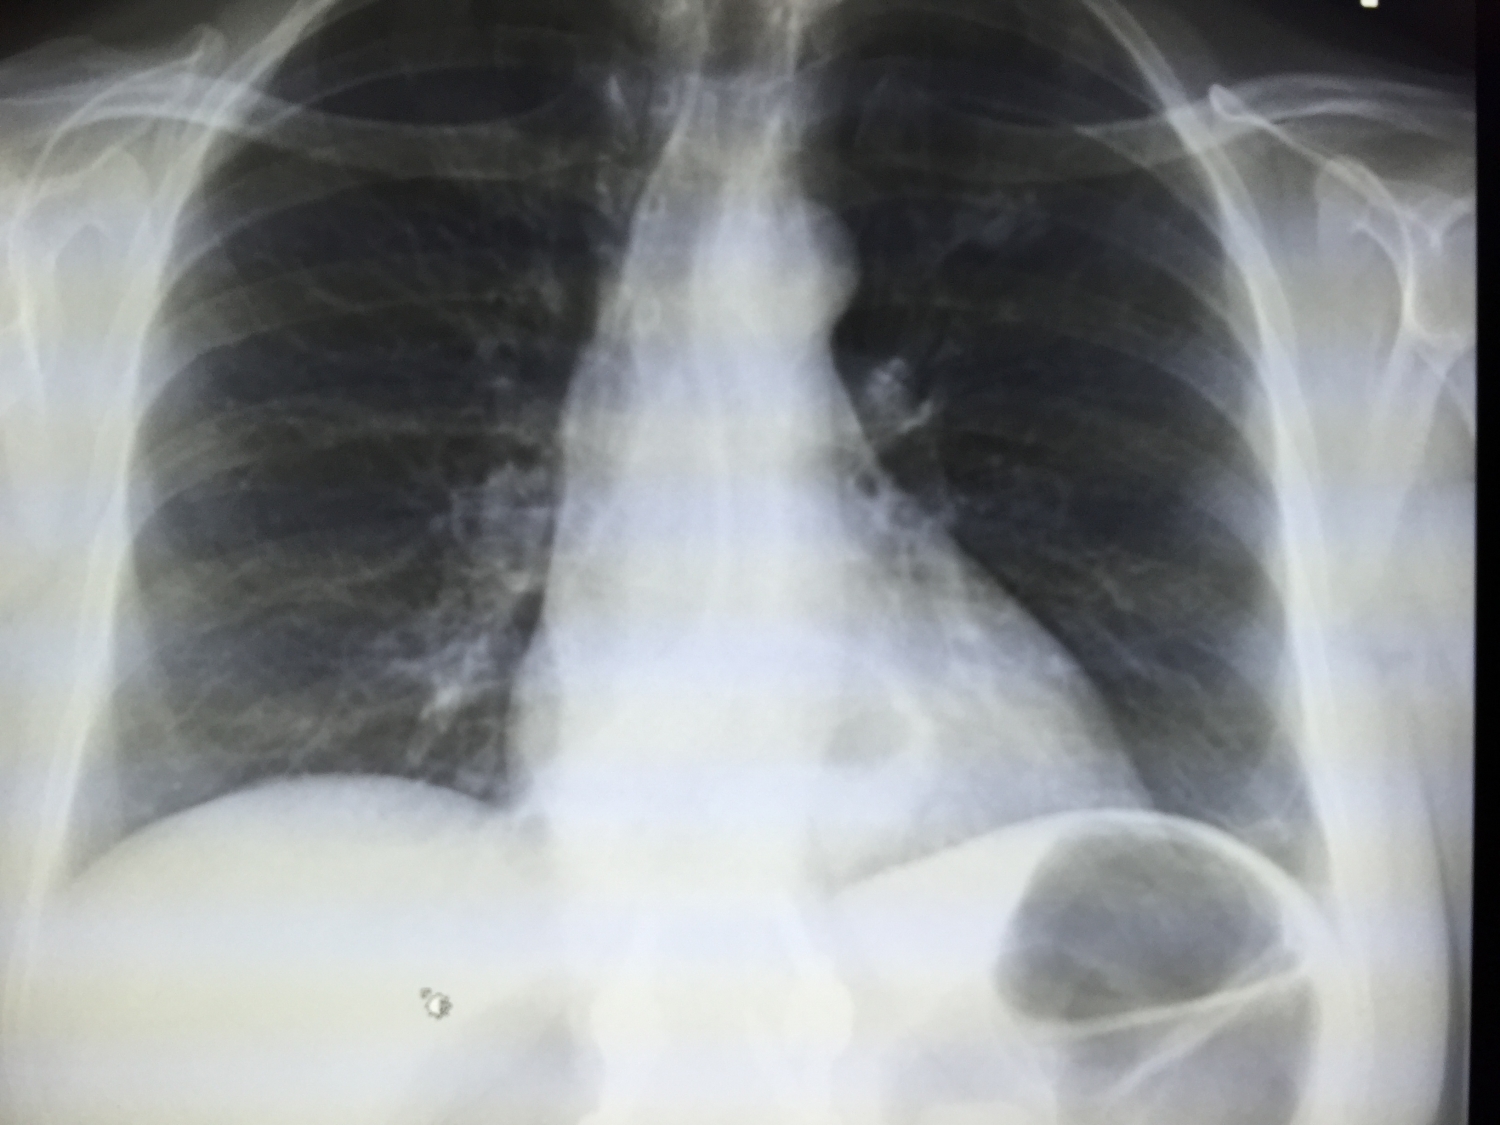

Chest Xray showed atelectasis of the lower part of the left lung with What Is The Diagnosis Of A Chest X Ray Shows Atelectasis If the cause is not clinically apparent, bronchoscopy or chest computed tomography may be. Web lung atelectasis (plural: Treatment varies depending on the cause and severity of the atelectasis and may. Web if imaging is warranted, chest radiography, chest computed tomography, or thoracic ultrasonography are useful when diagnosing. Atelectases) refers to the collapse or incomplete expansion of pulmonary. Your healthcare. What Is The Diagnosis Of A Chest X Ray Shows Atelectasis.